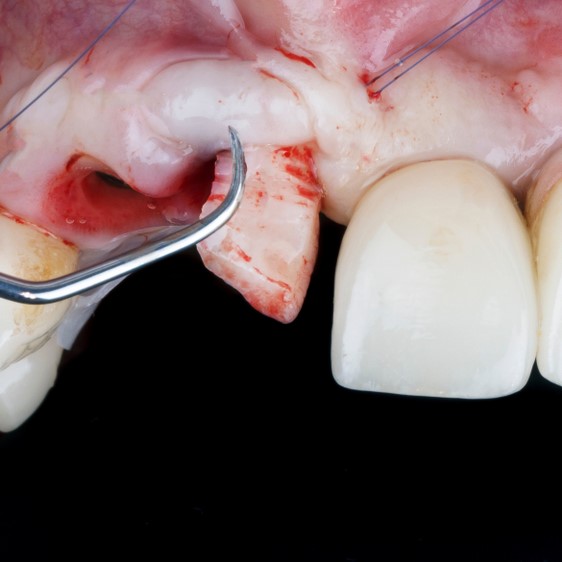

Twenty-five consecutive patients who had impacted mandibular third molars were selected. The attending surgeon wore an operation gown and visor mask, and carried out the tooth extraction with the regular procedure. We counted the number of bloodstains found on the operation gown and visor mask, and confirmed the presence of diluted and invisible bloodstains using a leucomalachite green presumptive test, which was able to detect dilutions up to 1:4,000.

There were 469 separate bloodstains on the gown and visor mask of oral surgeons, which came from 19 (76%) of 25 patients during impacted mandibular third molar surgery. Presumptive tests for invisible bloodstains resulted in 1,206 positive reactions, 2.57-fold greater than the visible stains, from 88% of the cases. All of the surgeons were right-handed and the common areas of staining were the right forearm, face, and thorax regions.

Dental procedures with high-speed instruments exposed surgeons to possible blood-borne infections by splashing in nearly 90% of the cases. Greater than 50% of the stains were invisible to the naked eye. Based on our results, strict compliance with barrier precautions, including routine use of an operation gown and visor mask, is recommended whenever oral surgery is carried out with high-speed rotary instruments.